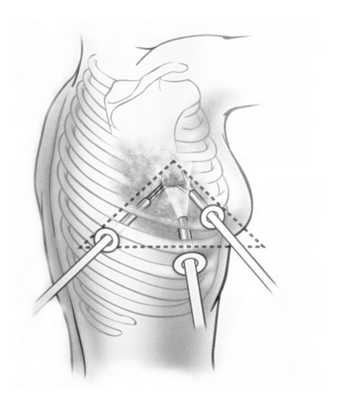

- Пациент снимает одежду с верхней половины тела, ложится на здоровый бок, под который кладут валик, руку поднимает к голове, мужчинам медсестра удаляет волосяной покров в области предстоящих проколов;

точки доступа при торакоскопии

Диагностическая торакоскопия может длиться до 2 часов, а торакоскопическая хирургическая операция — до 2,5 — 3 часов. После манипуляции пациента на некоторое время оставляют под наблюдением: на протяжении 1-го часа — каждые 15 минут, затем каждые полчаса, а спустя 3 часа после вмешательства — ежечасно. Если возникнет сильная болезненность, будут введены обезболивающие средства. В клинике придется провести от нескольких суток до 2 недель.